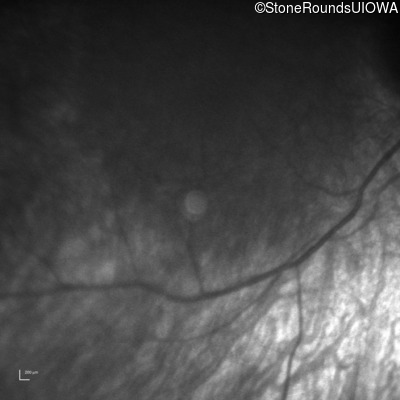

Infrared Fundus Photograph - Right -

Light Perception

Exemplar

Infrared Fundus Photograph - Left -